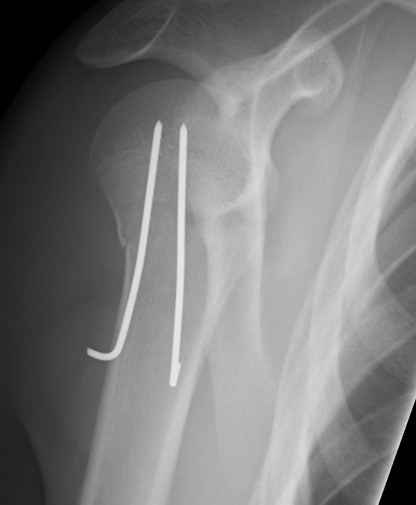

3. Retrograde flexible nails

TENS

Technique

2 x drill holes in lateral supracondylar ridge

- 1 cm proximal to lateral epicondyle

- pass 2 x TENS

- standard 0.4 of diameter of bone

- usually 2.5 mm

- radial nerve at risk